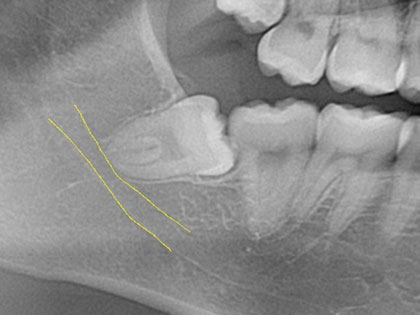

親知らずの抜歯 症例紹介